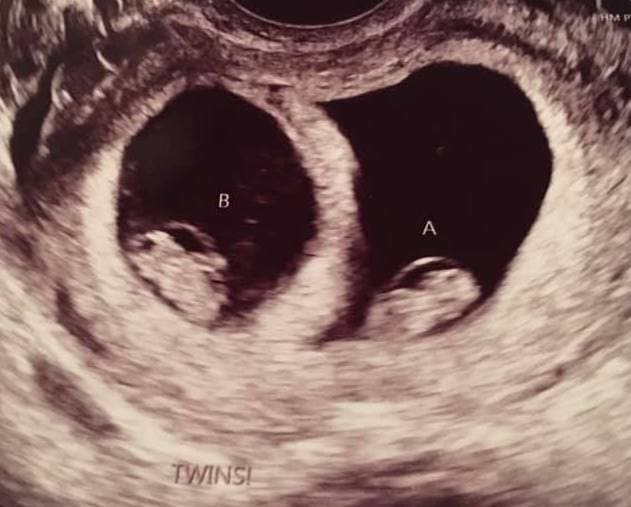

Early Twin Ultrasound at 7 Weeks

The earliest your doctor would likely order an ultrasound confirming twins would be 4 weeks pregnant. But unless you are going through fertility treatments, doing an ultrasound before 6 weeks isn’t very common, with the exception of complications. Women who are going through fertility treatments or have early complications may be able to have an early twin ultrasound at 4 or 5 weeks pregnant and find out they are pregnant with twins.

At four to five weeks after a pregnant woman’s last period the ultrasound commonly shows a small collection of fluid within the lining of the uterus that represents the early development of the gestational sac. At about five and a half weeks after a pregnant woman’s last period the ultrasound typically shows a gestational sac and within it we can see a 3-5 mm bubble-like structure, which is the yolk sac. At approximately six weeks after a pregnant woman’s last period, we can see a small fetal pole, one of the first stages of growth for an embryo, which develops alongside the yolk sac.

Yes! You’d need to have an ultrasound at 7 weeks to confirm a twin pregnancy. Your twin belly at 7 weeks may not look like much of a belly at all, so getting in to your doctor for an ultrasound is key to find out if you’re really having twins.